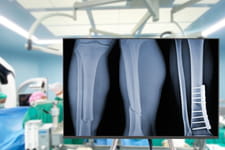

Effectuée par un chirurgien, l'opération chirurgicale est une pratique médicale qui permet d'atteindre et d'intervenir sur un organe interne ou externe. Le patient est placé sous anesthésie locale ou générale. L'opération est réalisée dans un bloc opératoire stérile, c'est-à-dire débarrassé de toute trace éventuelle de germe qui pourrait infecter le patient.

Liste et exemples d'opérations chirurgicales